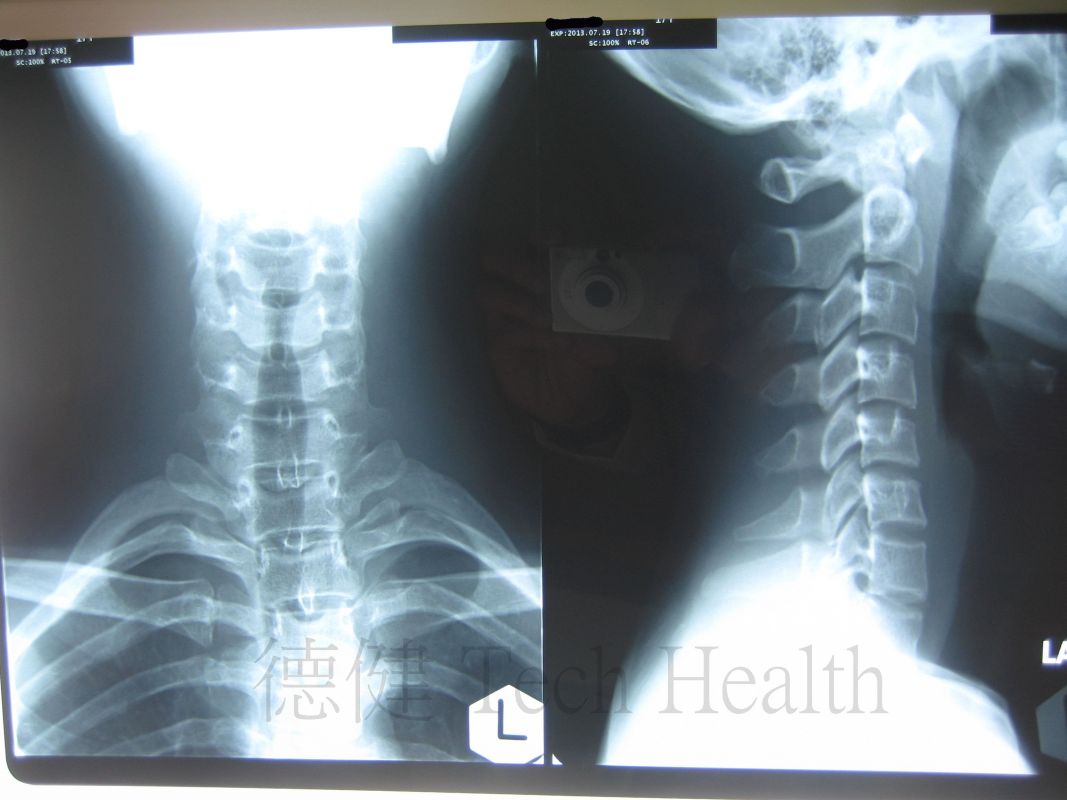

個案二 - 陳先生 18歲 - 胸椎側彎。

- 2013-7-29 患者時有困倦無力,肩背酸痛,頸胸椎活動受限,咳嗽或深呼吸時不適,胸悶胸痛,腹脹,下肢循環不佳,X片示胸椎側彎。集中治療頸胸椎及頭肩。